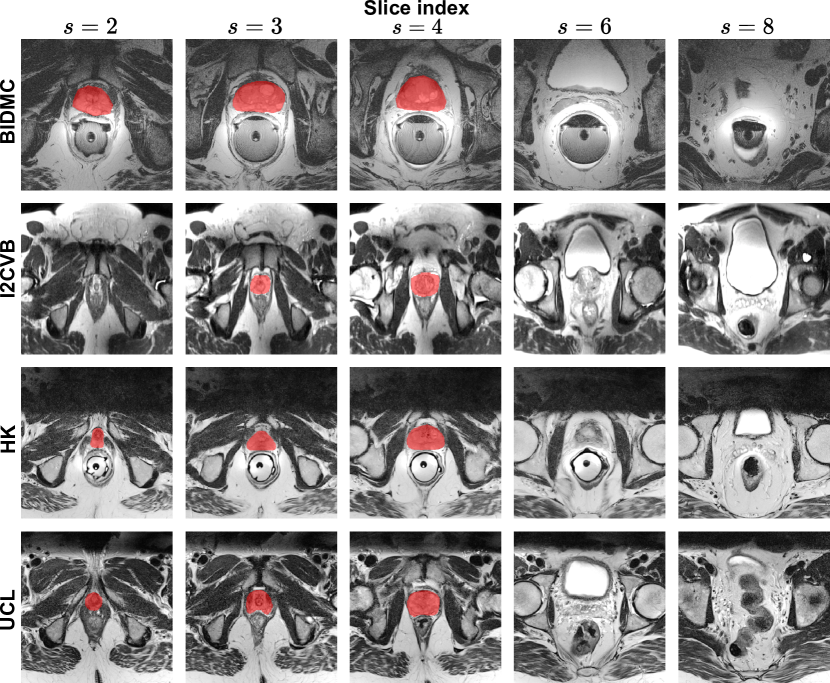

Data: Following previous work on medical continual segmentation [9, 10, 28, 27], we evaluate on the tasks of segmenting the prostate and hippocampus in, respectively, T2-weighted and T1-weighted MRIs. The hippocampus data consists of three datasets: Multi-contrast submillimetric 3 Tesla hippocampal subfield segmentation (Dryad) [19], Harmonized Hippocampal Protocol dataset (HarP[36] and the hippocampus data released for the Medical Segmentation Decathlon (DecathHip[1]. We train in the order DecathHip\rightarrowDryad following the setup in previous works [8]. We preserve HarP for OoD testing. The sets contain 260, 50, and 270 samples, respectively. The prostate data originates from five institutions using different devices and acquisition parameters [23]. We train in the order BIDMC\rightarrowI2VCB\rightarrowHK\rightarrowUCL, creating a challenging setting by starting with the smallest dataset and alternating between datasets with and without an endorectal coil. The segmentation mask encompasses the central gland and peripheral area. We likewise use the final dataset, RUNMC for OoD evaluation. Each dataset contains 12 to 30 samples and is randomly divided into 20%percent2020\% testing, 56%percent5656\% training, and 24%percent2424\% validation. A qualitative comparison of the data used can be found in Fig. 2. We also utilize synthetic OoD data. Here, we augment the test sets with common MRI artifacts (random bias field, spiking, or ghosting) doubling their size. A few examples of augmented MRIs are depicted in Fig. 3.

Figure 2: Representative slices s𝑠s of MRI scans from each (a) hippocampus and (b) prostate dataset. The red areas depict the ground truth segmentation masks.